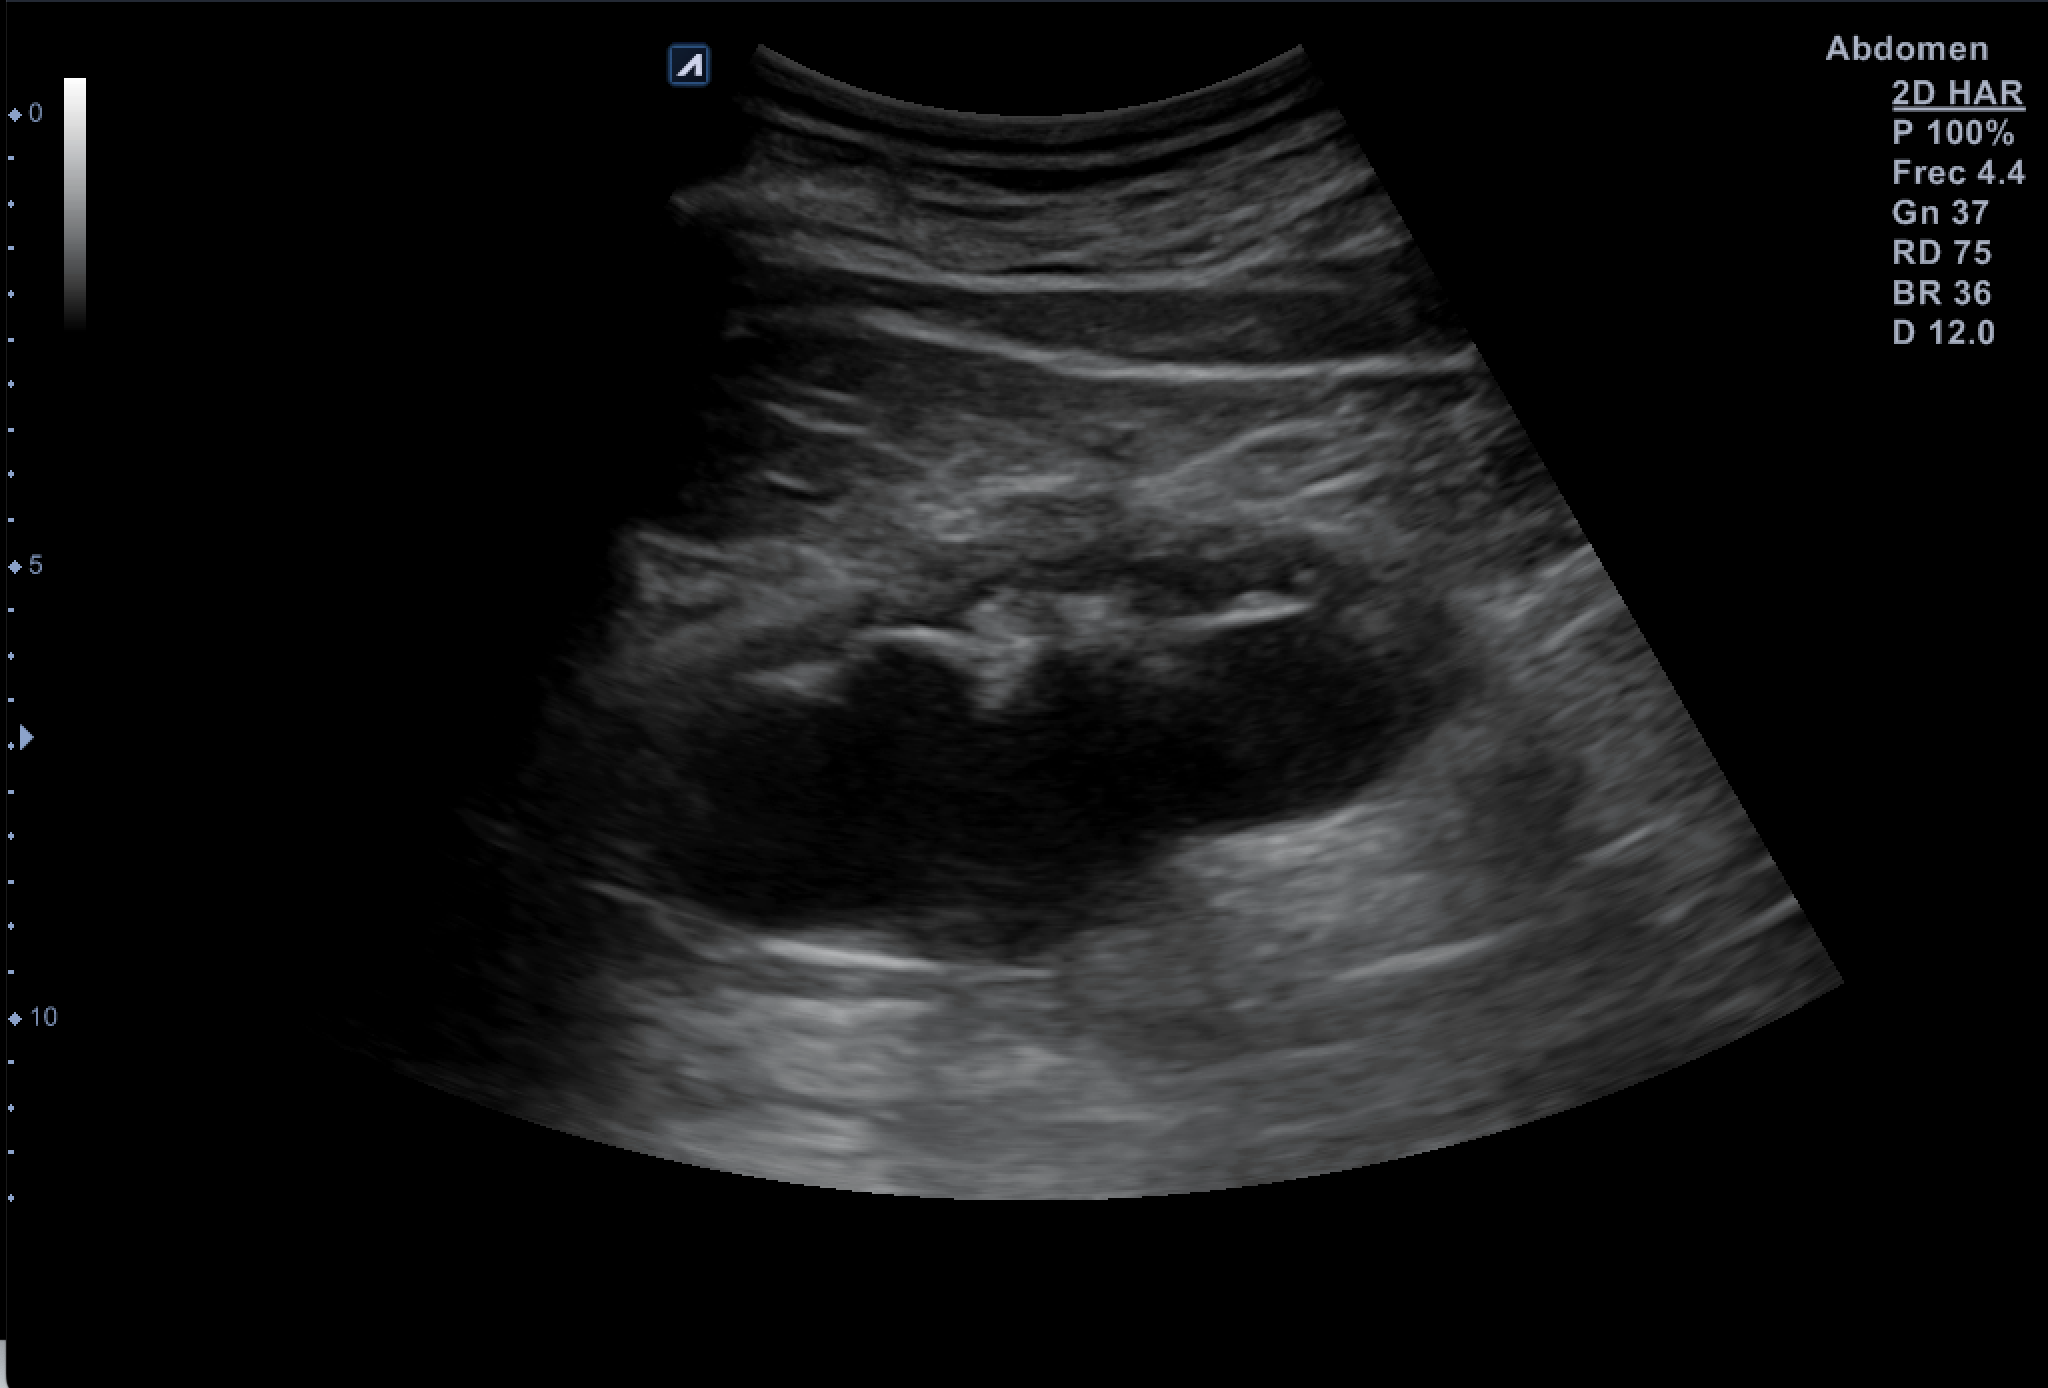

Hallazgos ecográficos

Tras valoración vesicoprostática con vejiga normal, jet vesicales visibles con próstata de 45 cc y residuo postmiccional mínimo. Riñón derecho como normal de tamaño y morfología sin dilataciones pielocaliciales (11 cm de tamaño). El Riñón Izquierdo (RI: 9 cm) presentaba una hidronefrosis grado IV y atrofia cortical con pelvis renal distendida, no consiguiendo detectar la causa obstructiva y considerando la posibilidad de una estenosis de la unión pieloureteral y como segunda opción una litiasis  ureteral pese a la normalidad de los jets vesicales.